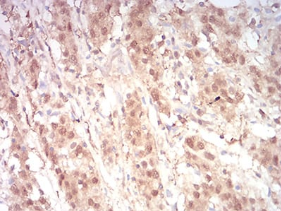

IHC    1/200 - 1/1000